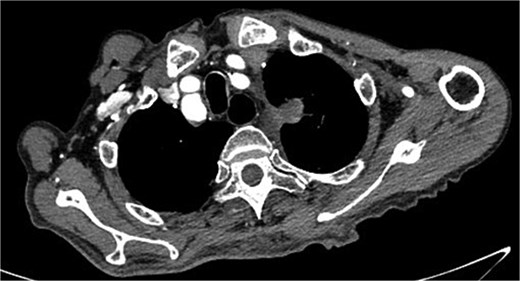

Despite recovery, the patient remained physically exhausted and required ongoing rehabilitation. In May 2023, after a COVID-19 infection, the patient experienced blood in phlegm. CTA confirmed successful aneurysm repair with no endoleak (Fig. 3). Thus the patient was hospitalized in the respiratory department. Relevant pulmonary examination indicators and lung CT results revealed no lung lesions associated with blood in sputum (Fig. 4). However, throughout July, 2023, intermittent blood in phlegm continued, and a CTA on July 19, 2023, revealed a type IV endoleak (Fig. 5). Conversely, aortography on July 27, 2023, showed no obvious endoleak. Closed drainage of the left thoracic cavity was performed, but blood in phlegm recurred on August 9, 2023. A Gore C-TAG stent graft was deployed in the thoracic aortic arch, with its proximal end anchored at the ostium of the left subclavian artery stent graft to ensure complete coverage of the endoleak site both proximally and distally(Fig. 6). Post-surgery, blood in phlegm symptoms abated.

The thoracic aorta was re-implanted with a covered stent graft to cover the breach.